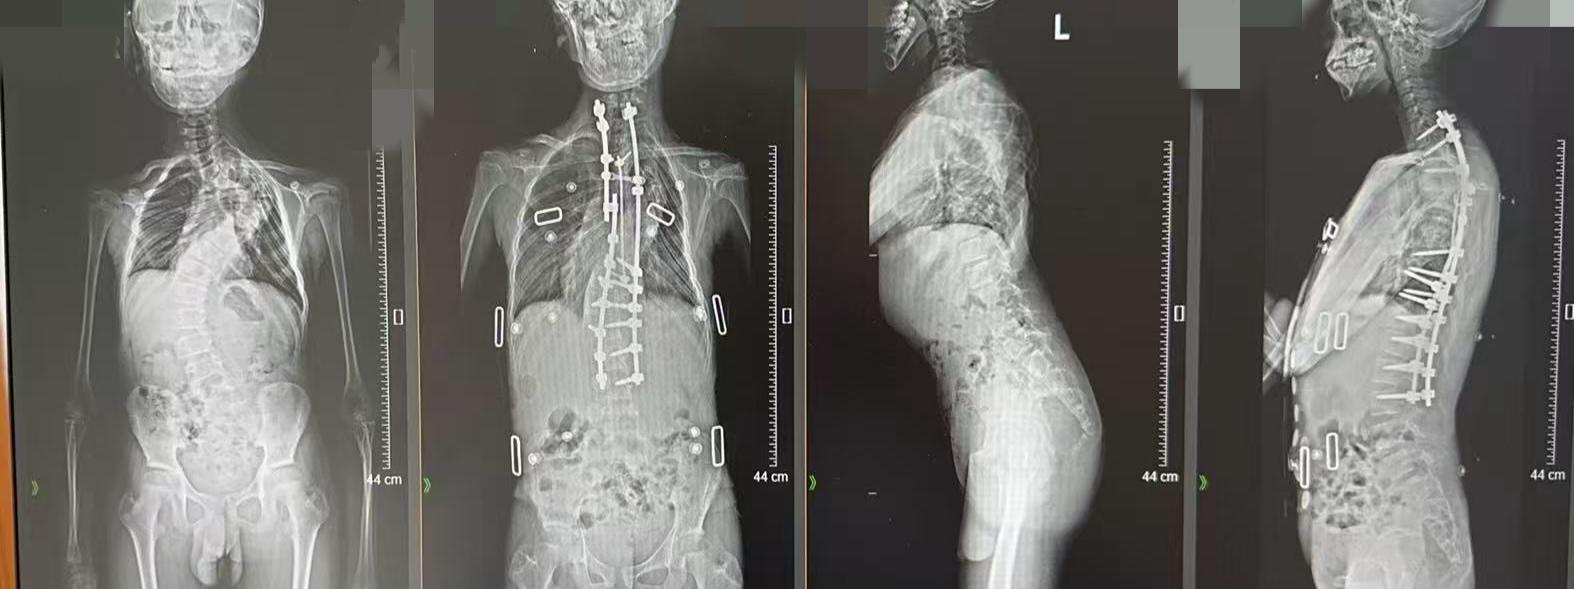

导致这些症状的元凶,是一种罕见的神经纤维瘤病。阿文的母亲曾带他辗转多家医院,检查结果显示,他的脊柱侧弯角度已接近150°,这种程度的侧弯会让脊柱呈现出明显的“C”形凸起。并且,阿文椎弓根纤细、椎管扩张、肋骨头脱位紧邻脊髓,手术致瘫风险极高。

影像显示,阿文的多个胸椎椎体之间形成一个近150°的“Ω”形侧弯,旋转严重,同时伴有椎体萎缩、椎弓根变细、椎管扩大及硬膜扩张。

经过近两年的系统治疗,阿文终于迎来了“生长棒毕业”的时刻。王亮团队为其进行最终矫形手术,术前通过3D打印技术精准规划方案,术中在机器人辅助下,于纤细、畸形的椎弓根上精确置入螺钉,对无法置钉的椎体则采用椎板钩固定。

在神经电生理监测下,团队运用超声骨刀对畸形严重区域截骨、松解,最后安装矫形棒进行矫正与平衡重建,并在顶椎区连接卫星棒加固。术前身高仅141厘米的阿文,历经4次手术后,身高达到了157厘米。